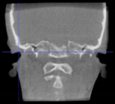

Three points determined the Acta plane: O, F right (FR), and F left (FL) (Table 2). Point O is the midpoint between the most craniodorsal point of the dorsum Sella and the most posterior dorsal point of the Basion in the midsagittal plane (Figure 1). Both points F are a result of the intersection between two lines: the line that connects the most inferior points of the lower orbital margins, right and left, and a line perpendicular to this line that runs through the most external points of the orbital margins, right and left (Figure 2). The new transverse reference plane, the Acta plane (Figure 2), is created by connecting the O-point (Figure 1) with FR and FL (Figure 2).

Figure 2.

(A) Construction of the F-points (right and left), frontal view. The F-points are originated from the intersection between the line connecting points A (the most inferior point of the lower orbit) and the perpendicular line to it that passes through points B (most external/lateral point of the Orbita). (B) Transverse view of the ACTA plane.